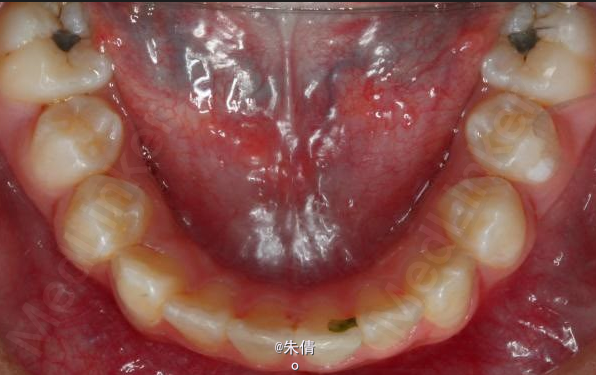

对于面型较好,拥挤度不大的病例,推磨牙向后不失为一种很好的方法,当然现在推磨牙后向的手段和方法很多,但是主要 是适应证的问题。我认为我们在做推磨牙向后,首先是考虑拥挤度,第二个要考虑的是现有的面型,第三点也是很重要的一点,是考虑牙弓后段拥挤度,Tweed-Merryfireld拥挤度的诊断方法将牙弓拥挤度分析分为三段,牙弓前段拥挤度,牙弓中段的拥挤度,以及牙弓后段的拥挤度。不管用什么方法或是手段推磨牙向后,一定不能将牙弓前端矛盾移到牙弓中段或是后段。今天给大家看一直面型,拥挤度不是很大推磨牙向后的病例。希望对大家能有所帮助。